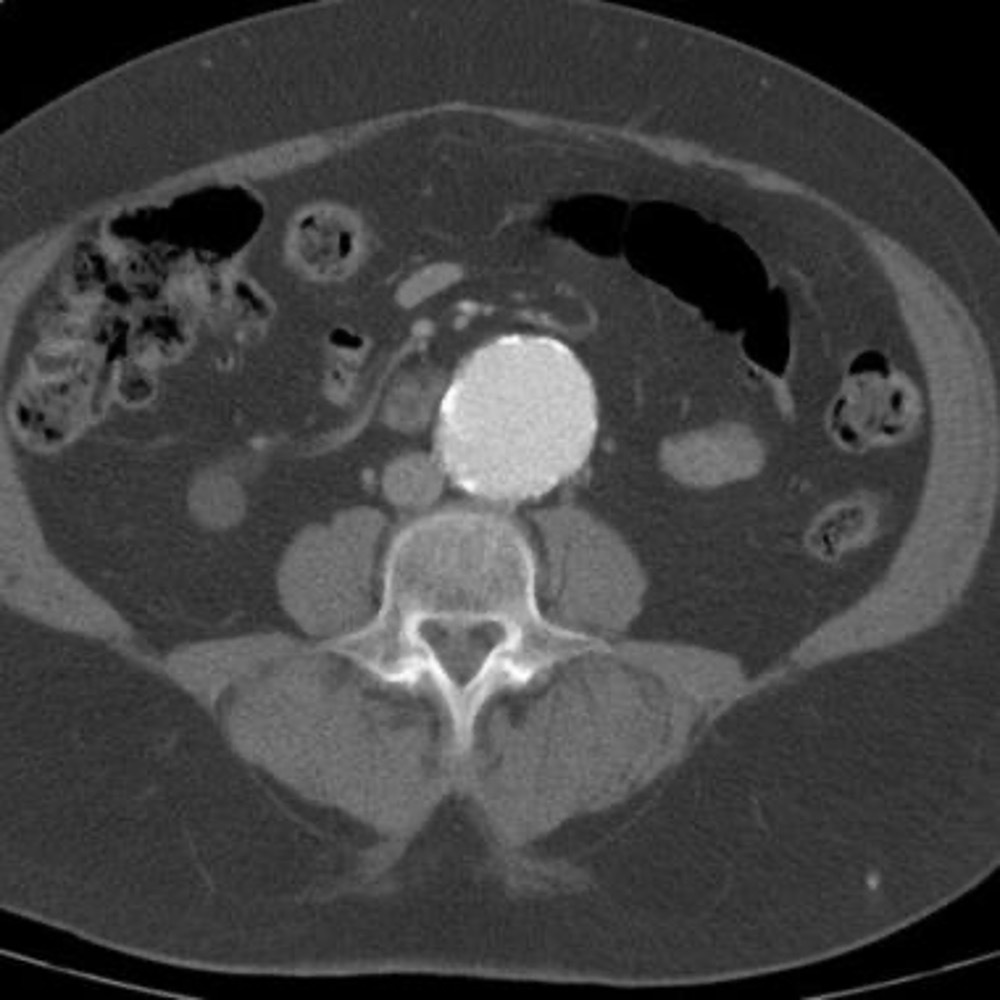

AAA

Ruptured AAA

Autosomal dominant polycystic kidney disease ## Footnote CT of the abdomen (coronal reformats) demonstrates both kidneys to be markedly enlarged by innumerable cysts ranging in size from a few millimetres to multiple centimetres. These cysts also vary in density: most are near-water density, some are hyperdense, others are calcified. Also present are numerous cysts in the liver. The pancreas is unremarkable. Features are consistent with autosomal dominant polycystic kidney disease, which was subsequently confirmed.

Sigmoid volvulus ## Footnote dilation causes the classic coffee-bean sign, a pathognomonic of sigmoid volvulus.